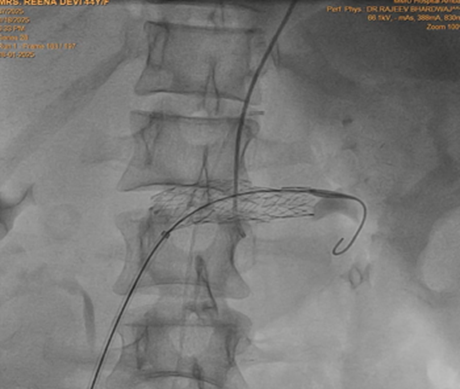

Keeping in view the possibility of Nutcracker syndrome (NKS). patient was taken up for percutaneous treatment. Right femoral vein puncture was done. Femoral vein angiography was done to see inferior vena cava (IVC), (Fig.1) to have idea of origin of left renal vein. Femoral artery access was also taken and left renal arteriography was done to trace renal vein in venous phase, but it could not be visualised. Since renal vein was not visualised, blind entry was done with terumo wire passed through right Judkins (JR)catheter. Catheter was then negotiated into LRV and venography was done (Fig. 2). It showed markedly dilated left gonadal vein (LGV), and left ovarion vein (Fig 3). Hardly any contrast was entering into IVC, due to compression by superior mesenteric artery (SMA). It was decided to put a stent in LRV across the compressed segment. To properly define the site of obstruction and stent placement, a JR catheter was placed in SMA (Fig 4), from left brachial artery approach. Self-expanding venous stent was then deployed, size 14x 60 mm. (Fig 5). LRV angio was then done which showed free flow of contrast into IVC and minimal reflux into LGV (Fig. 6). If, large reflux persisted, then coiling of LGV would have been required.

Figure 5: Self expanding stent placed in left renal vein across the superior mesenteric artery crossing.

Surgical treatment is recommended in patients with severe hematuria, severe proteinuria, varicocele, renal failure and severe pain. Endovascular stenting was first described as therapy for NKS in 1996 and results are good [8,9]. 6-8 Cm long stent with diameter of 12-14mm is placed near the first division of left renal vein to prevent stent migration. If significant reflux persists into the LGV after stent placement, then embolization of LGV may be required. Stent migration, erosion into adjacent structures, and kinking are the most common complications of endovascular procedures.